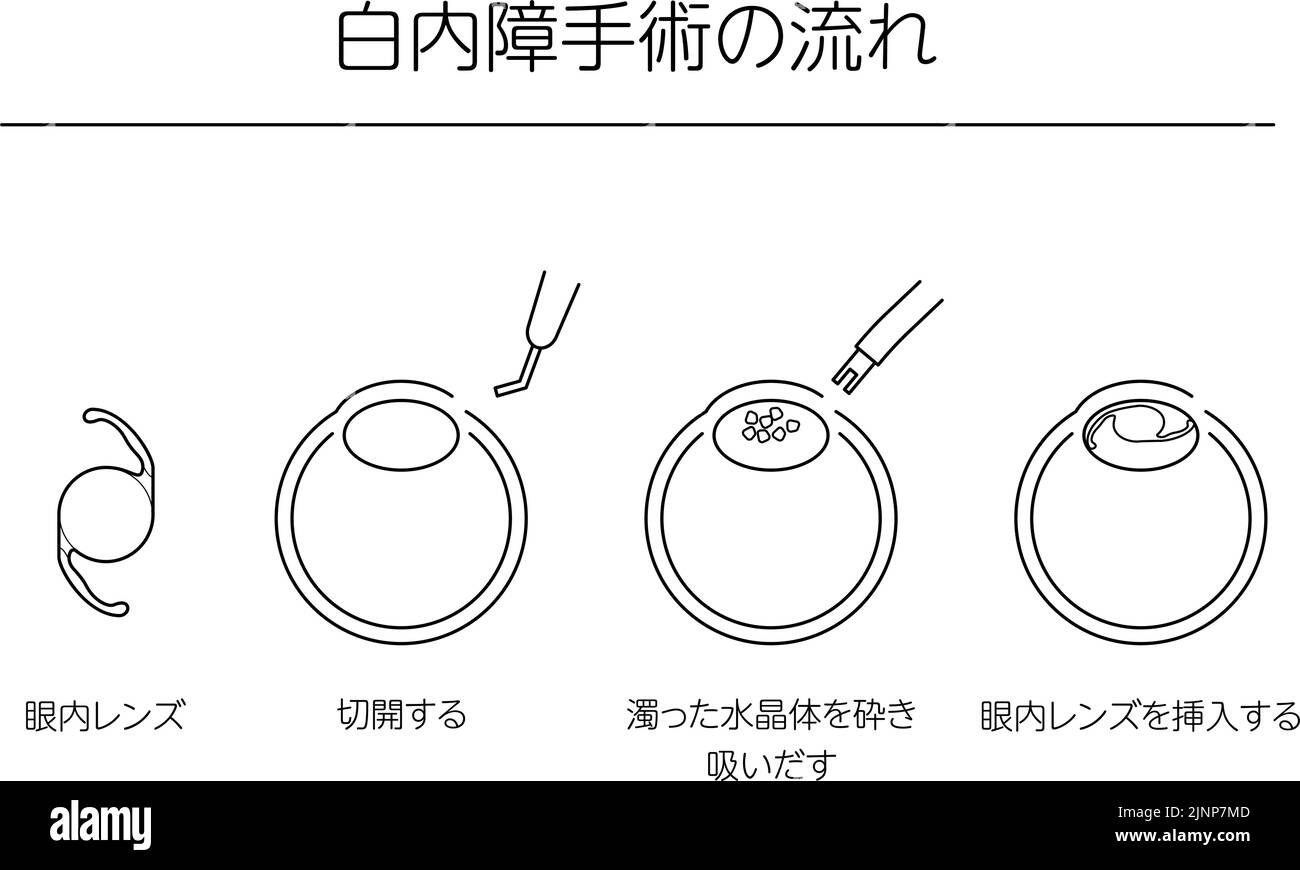

Flow of cataract surgery, illustrated illustration (line drawing) - Translation: flow of cataract surgery, intraocular lens, making incision, sucking Stock Vectorhttps://www.alamy.com/image-license-details/?v=1https://www.alamy.com/flow-of-cataract-surgery-illustrated-illustration-line-drawing-translation-flow-of-cataract-surgery-intraocular-lens-making-incision-sucking-image478076717.html

Flow of cataract surgery, illustrated illustration (line drawing) - Translation: flow of cataract surgery, intraocular lens, making incision, sucking Stock Vectorhttps://www.alamy.com/image-license-details/?v=1https://www.alamy.com/flow-of-cataract-surgery-illustrated-illustration-line-drawing-translation-flow-of-cataract-surgery-intraocular-lens-making-incision-sucking-image478076717.htmlRF2JNP7MD–Flow of cataract surgery, illustrated illustration (line drawing) - Translation: flow of cataract surgery, intraocular lens, making incision, sucking